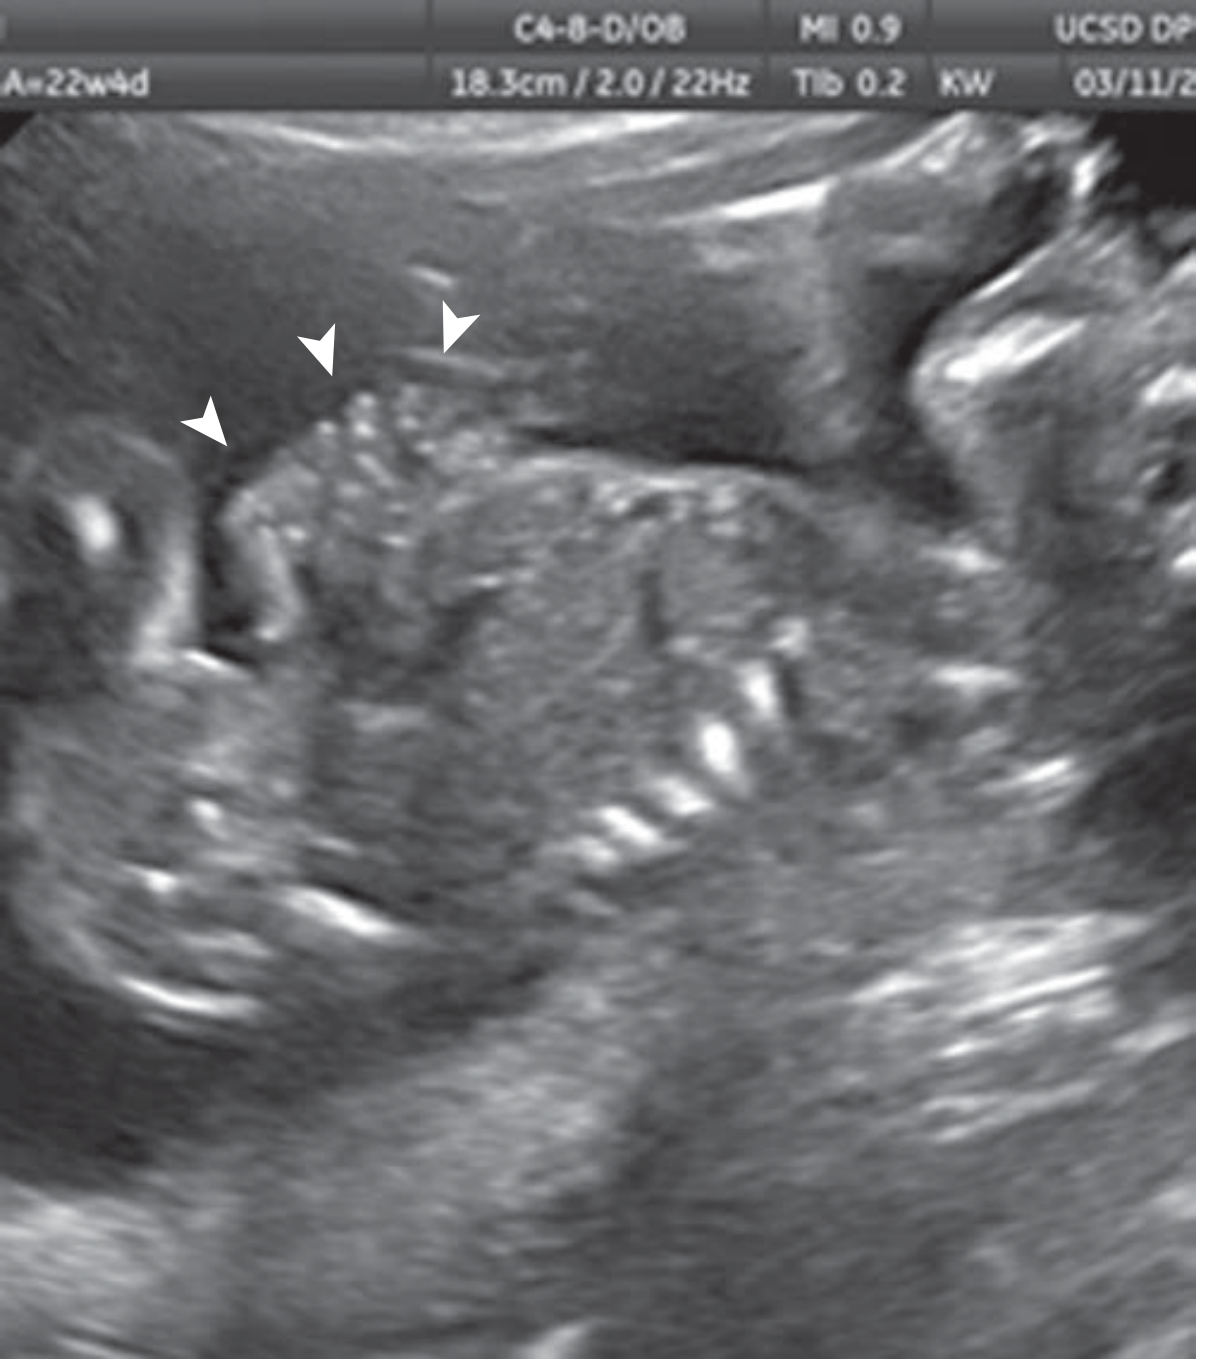

US at 22 weeks — "cauliflower" appearance of bowel loops floating freely in amniotic fluid (arrowheads)

Sagittal view at 22 weeks' gestation showing gastroschisis with typical "cauliflower" appearance. — Creasy & Resnik's, 9e

• Multiple loops of bowel floating freely in amniotic fluid — "cauliflower" appearance

• Defect at right side of abdominal cord insertion (color Doppler confirms)